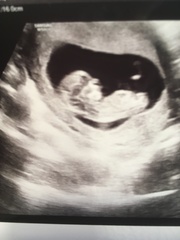

12 week scan this morning! T’was very exciting... happy healthy little bean measuring 11+5 which fits with my dates. Due 3rd of April. It was like a proper wee baby, all curled up asleep... the sonographer asked me to shake my hips to wake it up. Amazing to see it stretching its wee legs and arms and jumping around like ‘hey!! I’m sleeping, stop with the shaking!’ ☺️

@BeeKeeping awww lovely pictures!

Lovely picturesBee, good luck everyone for scans coming up :)

Aww @Beekeeping how lovely! Hi baby :)

Ahh that's lovely @beekeeping 😊

Lovely pics @Beekeeping! Good luck @Braverthanweare x